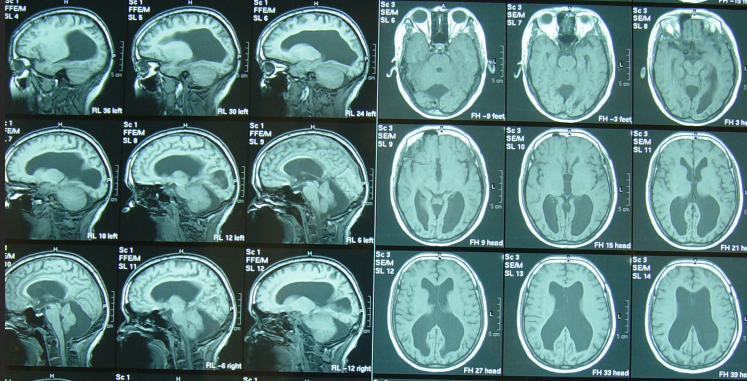

颅后窝蛛网膜囊肿神经系统影像鉴别

后颅窝蛛网膜囊肿

颅内囊肿1(蛛网膜囊肿)